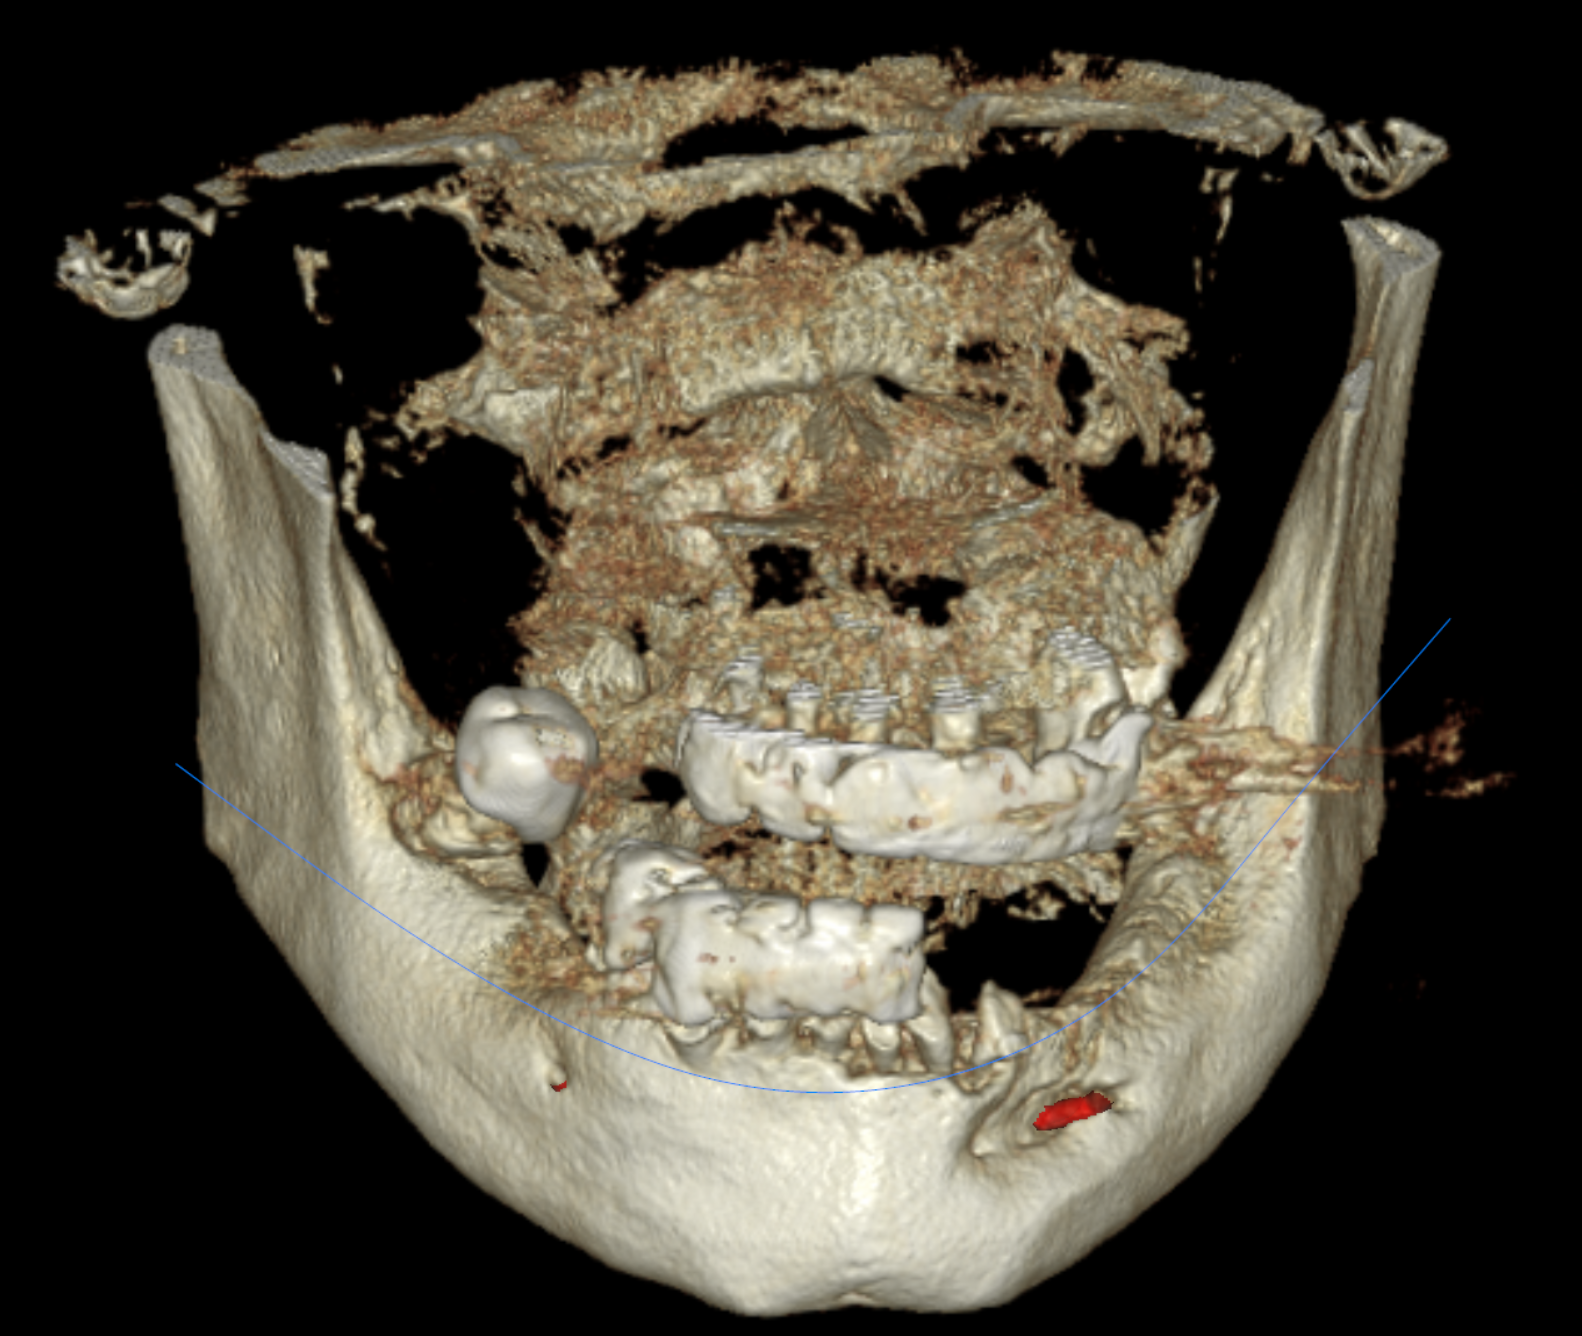

Cone Beam Computed Tomography (CBCT) scans were acquired for both the maxillary and mandibular arches. These scans provided critical insights into available bone volume, bone density, and anatomical considerations, forming a foundation for precise implant planning and guided surgery.

Bone was measured to asses the amount of bone gained and the density of the said bone and also a first simulation of implant placement was performed.

Another view of the post graft healing in the mandibular arch and visibility of the composite marker additions done on the upper denture for alignment purposes between scan image and CBCT datasets.

Implant placement planning done in EXOPLAN involved careful digital matching of the CBCT, wax-up, and facial scan data, resulting in an accurate, digitally-produced try-in prosthesis (Fig. 8). The validated prosthetic design was subsequently integrated with the software to plan placement of five strategically positioned implants in the upper arch.